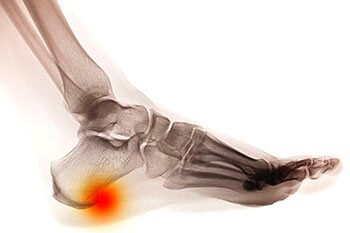

Heel spurs are brought upon by a calcium deposit that causes a bony protrusion on the underside of the heel bone. It normally forms over time and can best be diagnosed through an x-ray examination. Heel spurs are commonly linked with plantar fasciitis, an inflammation that runs along the bottom of the foot. Common symptoms of heel spurs include pain towards the affected area, inflammation, and swelling at the front of the heel.